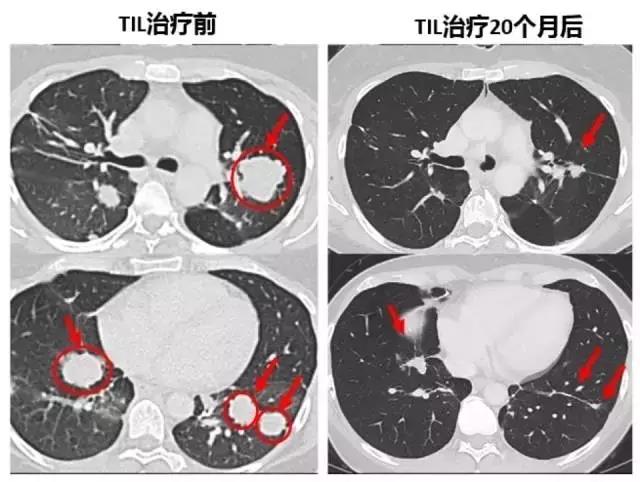

《自然医学》在线发表的研究:一位乳腺癌晚期患者已对其他治疗无反应,经过TIL免疫治疗后病灶竟奇迹般完全消除了,这是T细胞免疫疗法首次成功应用于晚期乳腺癌。

22个月后,这名患者的肿瘤(黄色箭头)消失得无影无踪(图片来源:《Nature Medicine》)